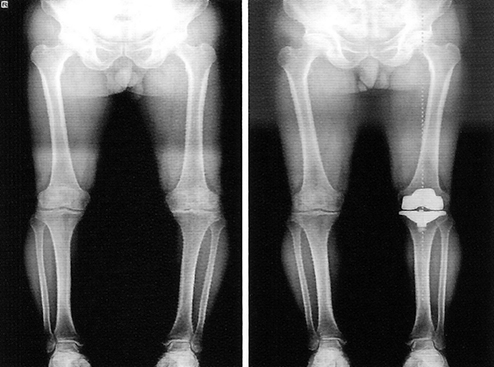

Рекурвация коленного сустава: рентгеновские снимки и объяснения